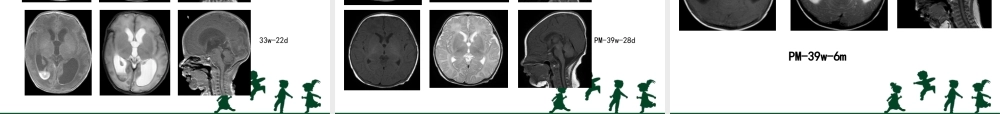

儿童康复的相关检查相关检查•1、CT•2、MRI•3、脑电图•4、听觉诱发电位•5、视觉诱发电位•6、肌电图•7、表面肌电图CT•影像学检查:直观显示脑结构的异常改变•部位:头颅、脊柱、颞部•检查需要睡眠CT优点•快速、安全、无创地显示脑的形态改变•对新生儿、早期脑损伤患儿有临床意义•对脑出血、钙化、骨化具有可靠的诊断意义CT缺点•具有辐射性,有一定的损害•分辨率较MRI差6轻度:散在或局限性低密度改变,在2个脑叶以内7中度:低密度改变超过2个脑叶,灰白质对比模糊中度不伴出血中度伴出血8•重度:弥漫性低密度改变,灰白质界限失,•脑室受压。中、重度HIE常伴ICH。颅内出血CT扫描弥漫性脑水肿室管膜下出血(箭头)左额叶局限性水肿(箭头)CT扫描脑室内积血(箭头)额叶白质水肿大脑弥漫性水肿蛛网膜下腔出血(箭头)MRI优点•良好的软组织对比、高分辨率、无创伤、无痛、无放射、可以多方位扫描,能够直观显示颅脑的形态学改变。•对白质的发育过程、脑白质病变有诊断意义•能对血管病变诊断MRI缺点•成像速度慢,运动伪影对,对婴幼儿睡眠要求高•钙化灶易漏诊头颅MRI脑室系统较小呈裂隙状,灰白质分界清楚,呈高低信号相间的柱状影,内囊后肢的后部及丘脑腹外侧均呈低信号正常足月新生儿基底节层面T2WI表现头颅MRI轻度HIE左顶叶局灶性水肿,T2WI信号增高,皮层变薄,灰白质分界欠清,而正常灰白质的高低相间的柱状影消失。头颅MRI重度HIE(生后3d)T1WIT2WI双侧大脑皮层深部呈线条状高信号双侧弥漫性脑水肿,白质信号增高,灰质变薄,灰白质分界消失头颅MRI重度HIET2WIDWI左侧顶枕叶大面积脑梗死(箭头),呈楔形高信号•蛛网膜与软脑膜之间•脑沟内T1高/T2低SISAH特点IVH-SAH-38w-7d蛛网膜下腔出血(SAH)Poorfd-PVH-SDH-38w20d8d脑白质损伤-出血(WMD-H)3d脑白质损伤-dPVL(WMD-dPVL)14d2m7m33w-22dIVH---脑积水33w-7dPM-39w-28dPM---脑积水PM-39w-7dPM-39w-6mPM---脑积水细菌性脑膜炎皮层受累---大肠埃希菌脑梗死---阴沟肠杆菌脑脓肿---白色念珠菌感染脑电图•电生理的一种•反映脑电波的情况•无创、安全•癫痫诊断的金标准脑电图国际标准10—20系统头皮电极放置位置。21个标准电极正常清醒及睡眠期脑电图EEG:48天婴儿清醒期。正常EEGEEG:48天婴儿清醒期。正常EEG听觉诱发电位•电生理•无损伤、客观性强、稳定性好•反映听神经功能的生理和病理现象•需深度睡眠定义•给予声音刺激,在头皮上所记录到由听觉神经通路所产生的电位ABR...